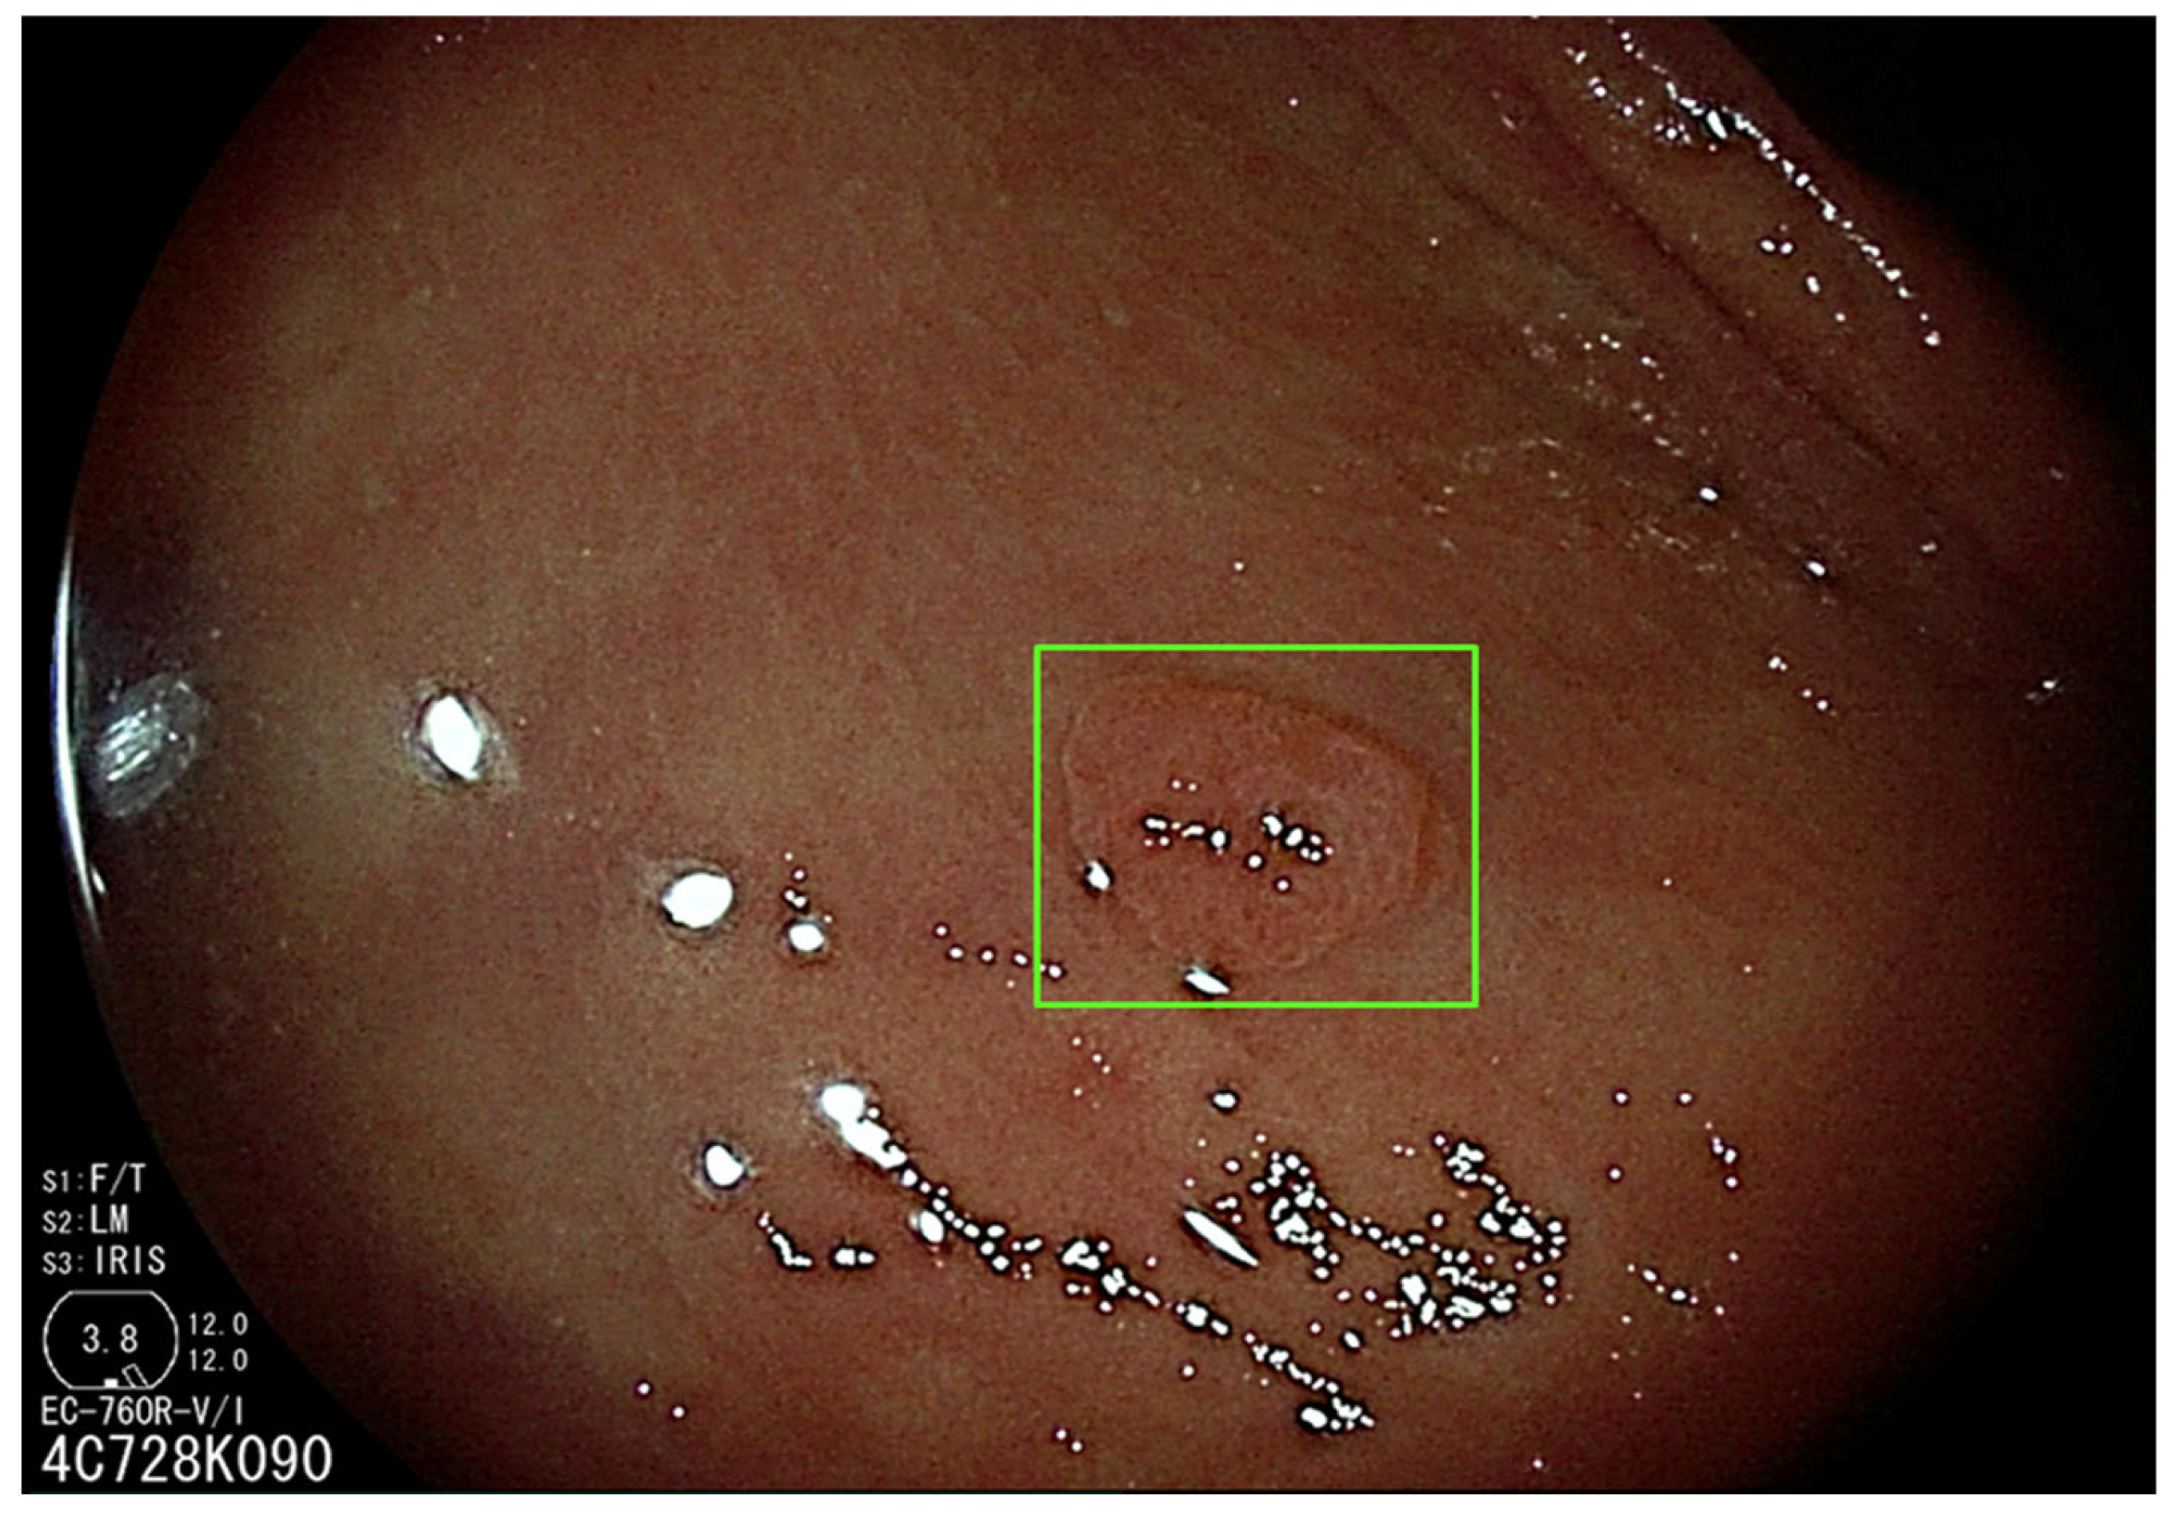

3.1. Artificial Intelligence-Assisted Detection (CADe)